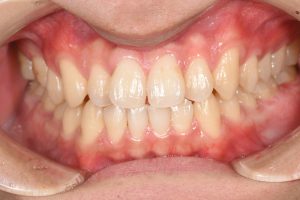

銀歯を全てセラミックにした症例

治療後